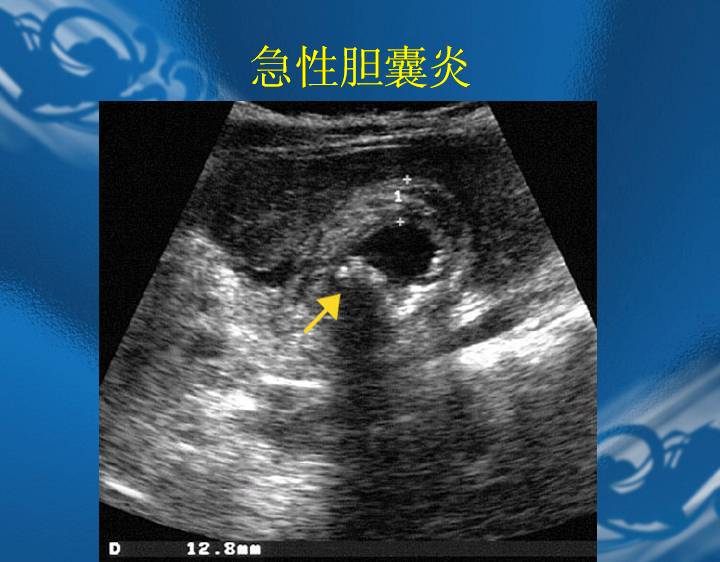

执业医师资格考试“实践技能”影像学辅导资料